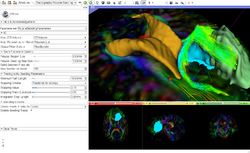

Slicer4 Neurosurgical Planning Tutorial

- The Neurosurgical Planning tutorial course guides through the generation of fiber tracts in the vicinity of a tumor.

- Author: Sonia Pujol, Ph.D., Ron Kikinis, M.D.

- Audience: End-users and developers

- Modules: Volumes, Editor, Tractography Label Map Seeding, Tractography Interactive Seeding

- Based on: 3D Slicer version 4.5

- The White Matter Exploration datasets contains a Diffusion Weighted Imaging scan of brain tumor patient.